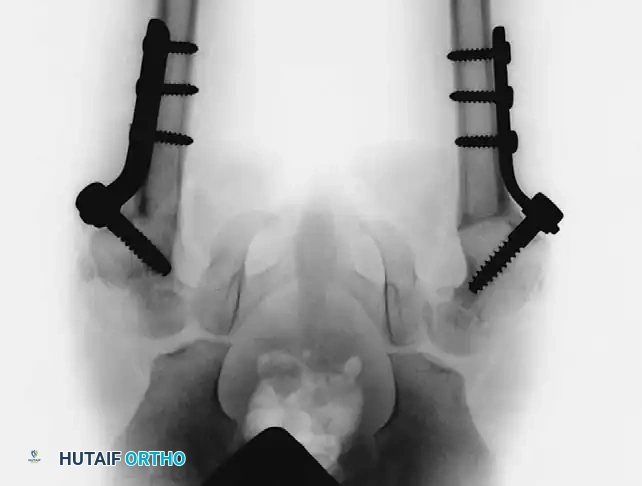

Surgical Technique: Valgus Osteotomy for Developmental Coxa Vara

Preoperative Planning: Meticulous templating is required to determine the exact angle of the lateral closing wedge needed to achieve a postoperative neck-shaft angle of 140 to 150 degrees, and a postoperative HEA of less than 38 degrees.

- Guidewire and Implant Insertion: If utilizing a pediatric screw and side-plate device (or a specialized pediatric blade plate), insert the primary guidewire into the midline of the femoral neck under strict biplanar fluoroscopic guidance (image intensification).

- Trajectory: Insert the screw as close as possible to the trochanteric apophysis without violating it, to avoid iatrogenic growth arrest.

- Depth: Ideally, center the screw in the femoral neck distal to the abnormal physis. If the neck is too short or dysplastic, the screw must be advanced across the physis and centered securely within the femoral head.

- The Osteotomy: Perform a transverse osteotomy slightly distal to the entry point of the screw, approximately at the level of the lesser trochanter.

- Deformity Correction: Resect a pre-calculated small lateral wedge of bone from the distal fragment. Reduce the osteotomy, bringing the femoral shaft into abduction to close the wedge, thereby correcting the neck-shaft angle to the targeted 140 to 150 degrees.

- Fixation: Secure the side plate to the femoral shaft using cortical screws in standard compression fashion. Ensure rigid internal fixation.